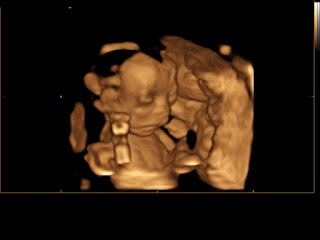

Best Moment This Week: The ultrasound was so wonderful! Leif and I were practically speechless the entire time since it was a lot to process. When little BB first appeared on their screen, he was gulping, but it looked like he was saying "hello" to us! He had his fists up by his face most of the time and wouldn't stop wiggling around, making it hard for them to get pictures at times! Everything checked out great and BB is developing as he should. The only issue is that my placenta is a little low - it's supposed to be 2 cm above my cervix, but it's only 1.6 cm. It's not too far off and might move up as my uterus continues to grow, but just in case, my doctor is monitoring me a little more closely. I'll have to have an additional ultrasound at 28 weeks to see how things are progressing, and based on a little research I did, it looks like I may be required to have a c-section if it the placenta ultimately isn't high enough. We'll see what happens! I'm just grateful and feeling blessed that everything else looked good. We weren't overly surprised that it was a boy - Leif and I both had very specific dreams that it was. I'm really looking forward to raising a little boy and Leif reminded me that I always used say "I'd love to have a little Leif around!"

What I’m Looking Forward To: Now that we know it's a boy, we've been really trying to hammer out some names and thinking about what it will be like to raise a son. I'm looking forward to everything we'll learn throughout this process and the different skills and interests we and the rest of our family and friends can share with sweet little BB. Knowing what his face looks like makes me so much more excited to snuggle him and hold him in my arms. From this point on, he'll start putting on fat and will start looking cuter and cuter every day!

And now for some ultrasound pictures and a couple videos!